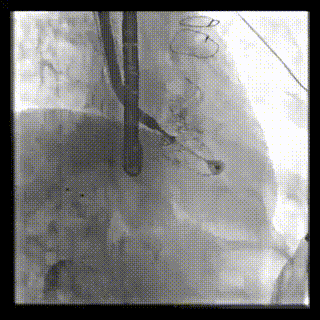

2021年12月24日,復(fù)旦大學(xué)附屬中山醫(yī)院葛均波院士團(tuán)隊(duì)成功應(yīng)用LuX-Valve Plus為一例極重度三尖瓣反流(TR)合并房顫、房缺的患者完成了經(jīng)血管三尖瓣置換術(shù),這是在前基礎(chǔ)上,本周完成的第三例經(jīng)血管三尖瓣置換手術(shù),葛均波院士、周達(dá)新教授等與心外科魏來(lái)教授、賴顥教授,心超室的潘翠珍教授、李偉教授及麻醉科的郭克芳教授共同完成了本周手術(shù),均獲得圓滿成功!患者術(shù)后超聲顯示無(wú)TR,臨床癥狀明顯改善。本周手術(shù)的成功也為L(zhǎng)uX-Valve Plus救治性臨床研究添上了濃墨重彩的一筆。

三例患者入院后,葛均波院士團(tuán)隊(duì)周達(dá)新教授、潘文志教授、張?jiān)床┦?、陳莎莎博士及心超室的潘翠珍教授、李偉教授?duì)患者的情況進(jìn)行詳細(xì)評(píng)估和討論,最終決定為三例患者選擇LuX-Valve Plus40mm、50mm和50mm型號(hào)的瓣膜進(jìn)行手術(shù)治療。手術(shù)后即刻拔除氣管插管,術(shù)后患者三尖瓣反流癥狀得到顯著改善,復(fù)查心超結(jié)果顯示人工三尖瓣瓣膜支架固定穩(wěn)定,瓣葉關(guān)閉形態(tài)未見異常,未見明顯反流。